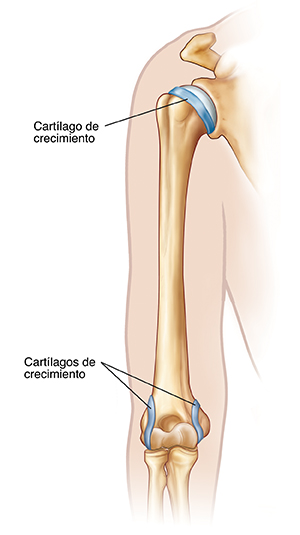

Hombro y codo Helico sales, Molestias en el hombro al empujar algo con la mano o brazo Dr Michell Ruiz Especialista en Hombro Codo Rodilla. Ciudad de Mexico. Hospital Angeles Metropolitano sales, RECONSTRUCCION ARTICULAR DE HOMBRO Y CODO OrtoClinica del Norte sales, Hombro y Codo Dr. Jose Luis Hernandez sales, Protecciones para codos y hombros nivel 2 conjunto de codos y hombros. Outlete.es sales, HOMBRO Y CODO Facebook sales, Ejercicios de hombro Traumatologia Hellin sales, Hombro y Codo Traumatologo Murcia Doctor Alonso Lison sales, HOMBRO Y CODO sales, Dolor en los hombros y codos Te digo varios ejercicios para prevenirlo tips sales, Fortalecimiento de hombros y codos sales, ANATOMIA Y FISIOLOGIA DEL SISTEMA OSEO sales, Unidad de hombro y codo Archivos Clinica DKF sales, Manejo del dolor de hombro y codo sales, HOMBRO Y CODO sales, Dr. Marlon Zeledon Ortopeda Cirugias de Codos Hombros sales, Traumatologo patologia hombro y codo Madrid Clinica MipSalud sales, Giro de hombros Codos doblados Yoga de cerca Skandha Chakra Secuencias de Yoga Beneficios Variaciones y Pronunciacion en Sanscrito Tummee sales, ORTOPEDIA HOMBRO Y CODO TRAUMATOLOGIA DR. CARLOS E. CAMPOS sales, Traumatologo para lesiones de hombro y codo en Almeria Claudio Vazquez Colomo sales, Onura Gunea SUFRES DOLOR EN TU HOMBRO O CODO IMPORTANCIA de la Estabilidad Escapular Omoplato La cintura escapular requiere de un gran trabajo de Movilidad Estabilidad y Fuerza. Y tras un sales, Hombro codo y muneca PPT sales, El Hueso entre el Hombro y el Codo y sus funciones Cirugia de hombro sales, Text Cuando su hijo tiene codo del lanzador u hombro del lanzador sales, El Hueso entre el Hombro y el Codo y sus funciones Cirugia de hombro sales, Traumatologia y Unidad de Hombro y Codo en Madrid Clinica DKF sales, Traumatologo patologia hombro y codo Madrid Clinica MipSalud sales, Terapia de mano hombro codo Academia de terapia de manos sales, Dolor en el Hombro Tipos de Dolor Causas y Tratamientos Dr Michell Ruiz Especialista en Hombro Codo Rodilla. Ciudad de Mexico. Hospital Angeles Metropolitano sales, Lo que debes saber sobre las lesiones en hombros y codos Hospital Internacional de Colombia sales, Dolor de hombro codo muneca y tratamiento OptiMMus sales, Lo que debes saber sobre las lesiones en hombros y codos Hospital Internacional de Colombia sales, Hombro y codo 1001813 VR3170L Sistema Esqueletico 3B Scientific sales, Hombro y Codo Clinica Ciudad del Mar sales, Lo que debes saber sobre las lesiones en hombros y codos Hospital Internacional de Colombia sales, Product Info: Hombros y codos sales.